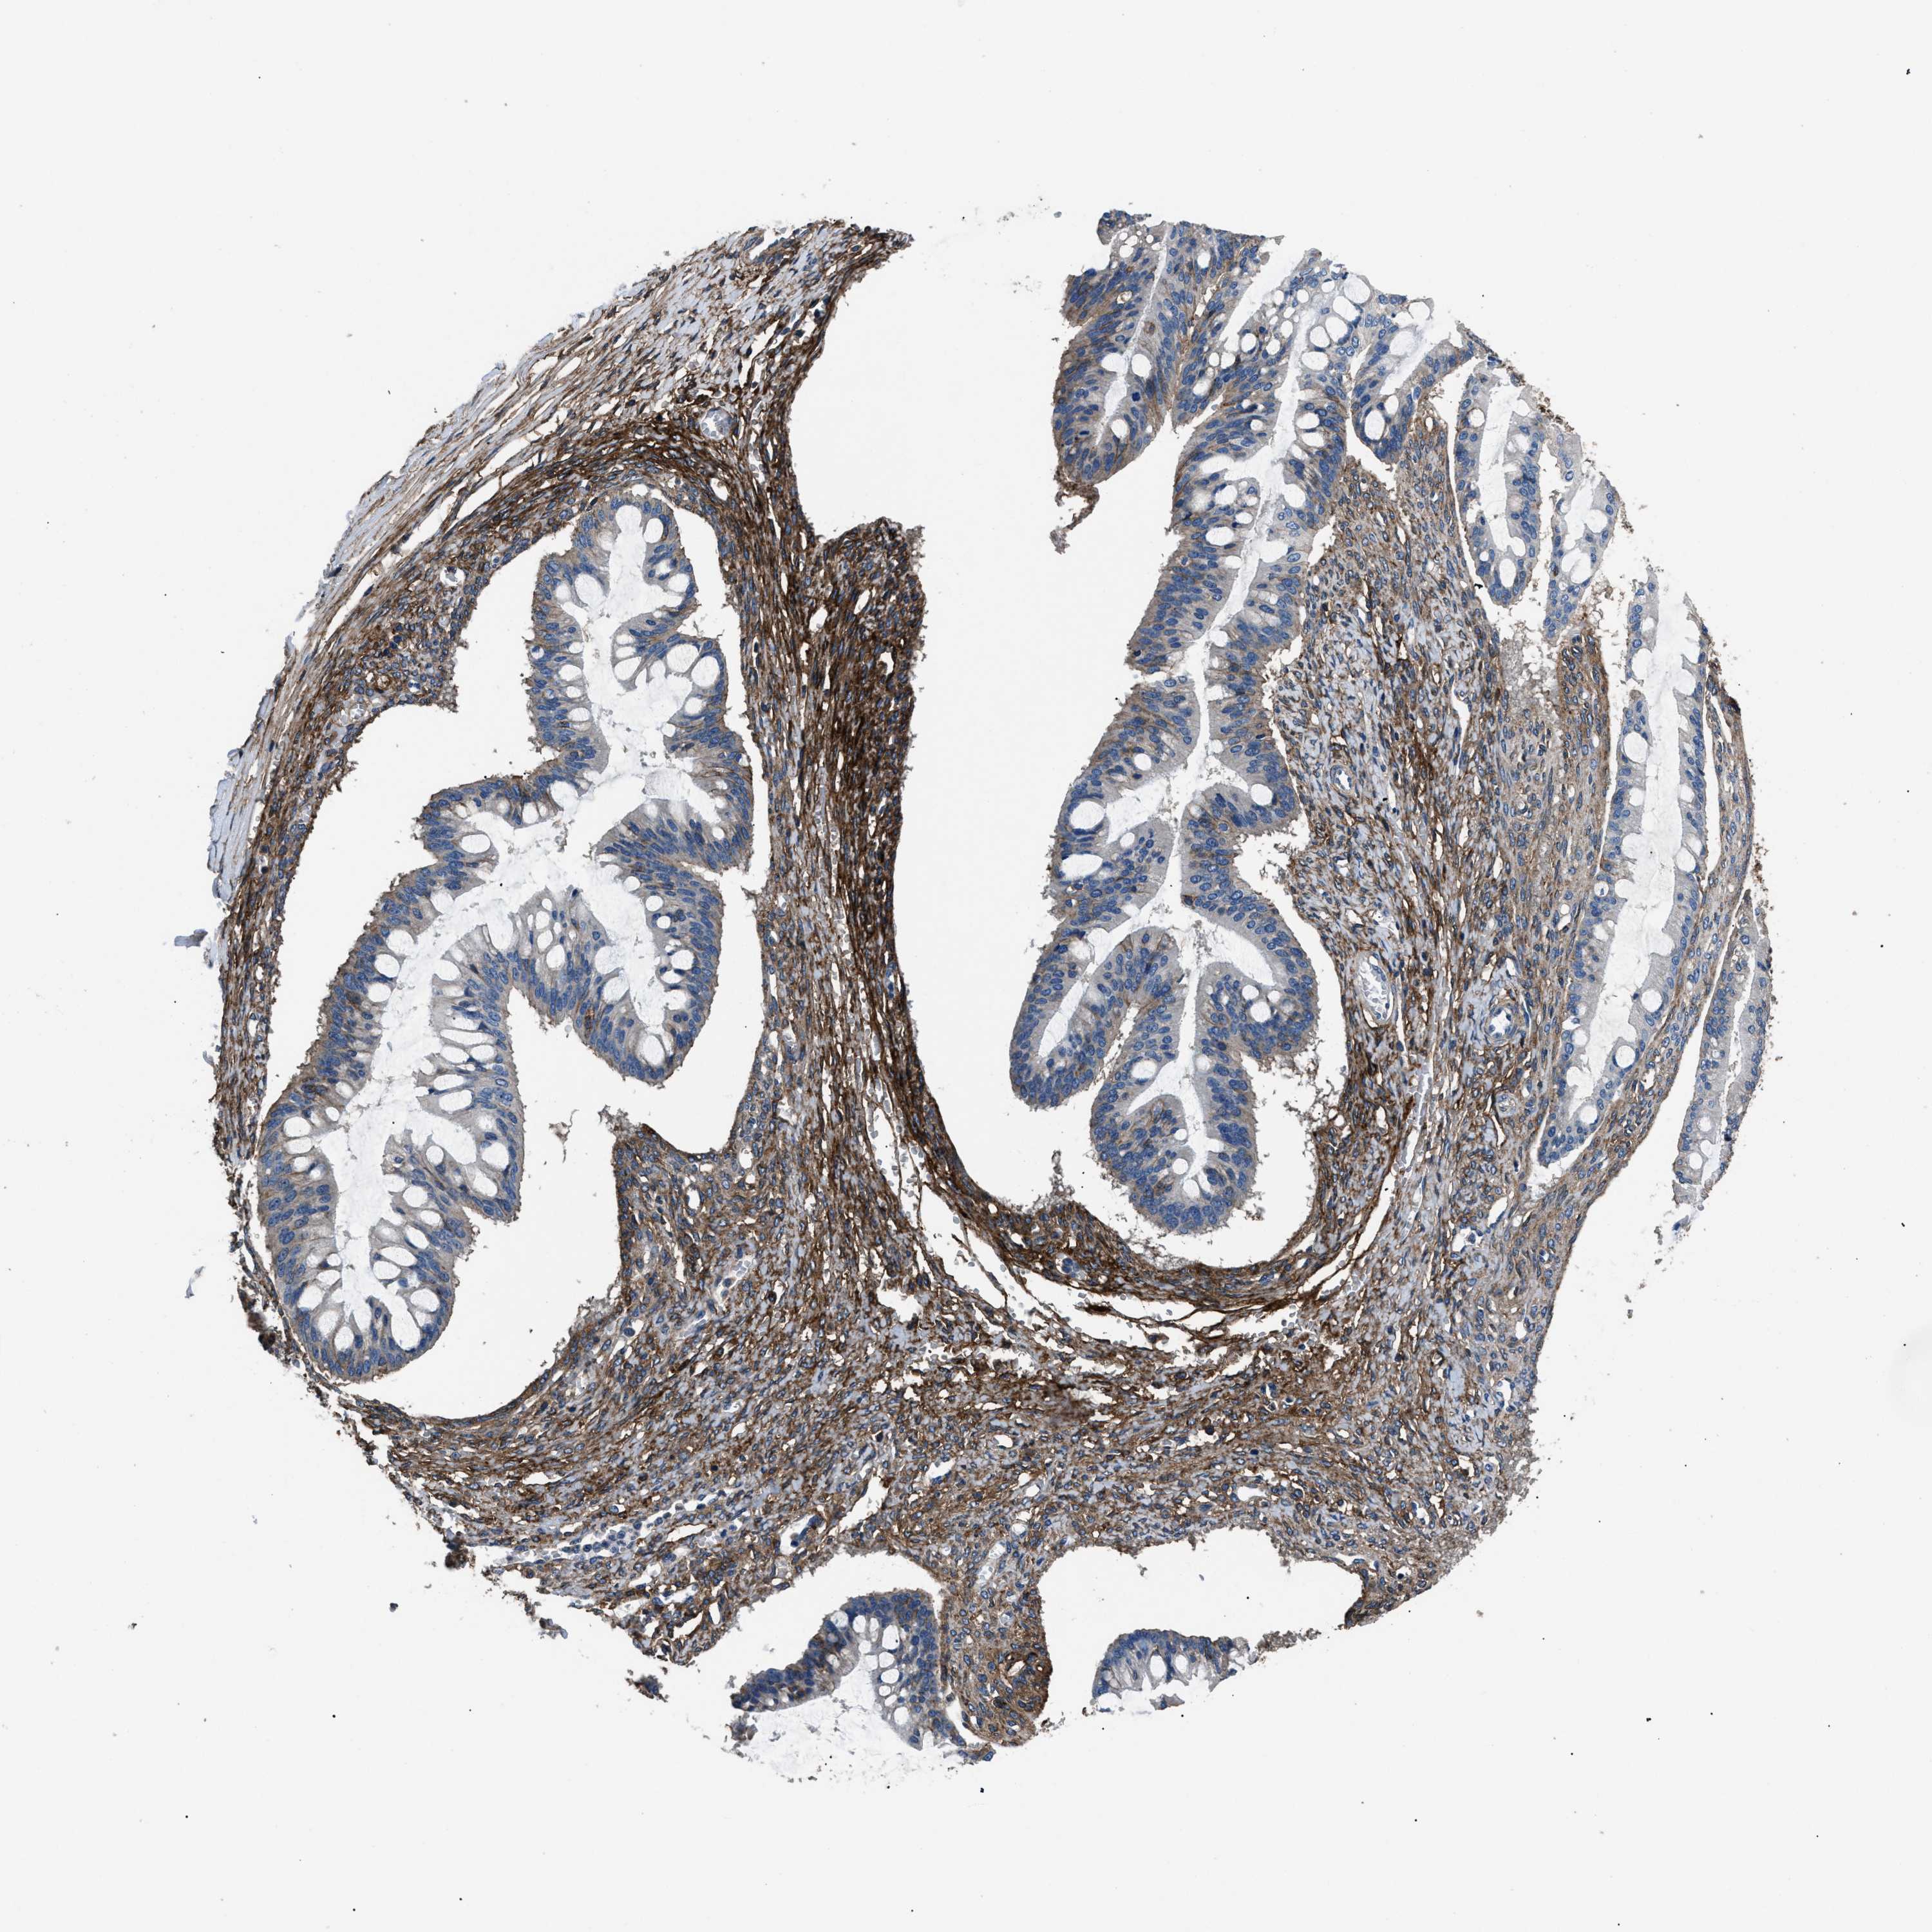

OVARIAN CANCER - Protein expressioni

A mouse-over function shows sample information and annotation data. Click on an image to view it in a full screen mode. Samples can be filtered based on level of antibody staining by selecting one or several of the following categories: high, medium, low and not detected. The assay and annotation is described here.

Note that samples used for immunohistochemistry by the Human Protein Atlas do not correspond to samples in the TCGA dataset.

Antibody stainingi

Antibody staining in the annotated cell types in the current human tissue is reported as not detected, low, medium, or high, based on conventional immunohistochemistry profiling in selected tissues. This score is based on the combination of the staining intensity and fraction of stained cells.

Each image is clickable and will lead to virtual microscopy that enables deeper exploration of all samples and also displays staining intensity scores, fraction scores and subcellular localization as well as patient and tissue information for each sample.

Antibody HPA009285

Antibody HPA017139

Antibody CAB017826

Cystadenocarcinoma, serous, NOS

Carcinoma, endometroid

Cystadenocarcinoma, mucinous, NOS

Carcinoma, NOS